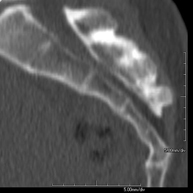

Prueba radiológica que consiste en obtener imágenes de las vertebras cervicales de alta definición anatómica mediante el empleo de un equipo de TC (Tomografía Computarizada). Indicaciones: cervicalgia sin/con irradiación a brazos, traumatismo.

Prova radiològica que consisteix en obtenir imatges de les vèrtebres cervicals d'alta definició anatòmica, mitjançant l'ús d'un equip de TC (Tomografia Computeritzada). Indicacions: dolor cervical amb/sense irradiació als braços, traumatisme, malformacions congènites. - TC Columna dorsal